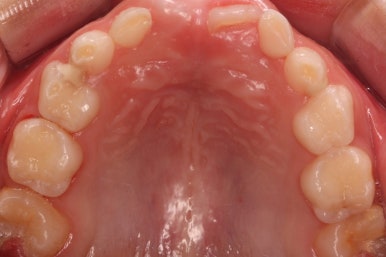

7개월 뒤 사진입니다.

해당 부위 어금니가 약간 나왔씁니다. 가장 간단하게 치료를 할 수 있는 상황이 되었네요.

매우 운이 좋았던 경우입니다.

장치를 부착했습니다.

할터만 장치(Halterman)는 굉장히 간단한 컨셉의 장치인데 매우 효율적입니다.

앞쪽 치아에서 반지처럼 둘러싸고 이를 이용해 어금니를 뒤로 쭈욱 당겨주면 끝.

단 3개월만에 제대로 못나오던 어금니 위치가 바로 잡혔습니다.

왼쪽이 부산어린이치아교정 키다리아저씨치과에서 치료하기 전 사진, 오른쪽이 후 사진입니다.

어금니가 잘 나온것을 확인할 수 있습니다.